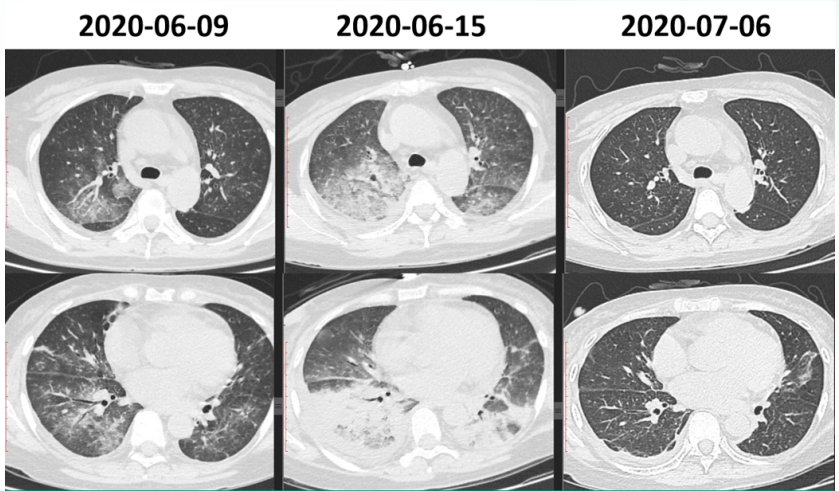

入院当天送KL-6快速进行性升高(图4)患者肺部后续出现机化和纤维化(图5)尽管整个治疗过程非常艰辛但最终预后比较满意。随访胸部CT可见病变吸收良好。

图片

5  患者住院期间胸部CT变化情况